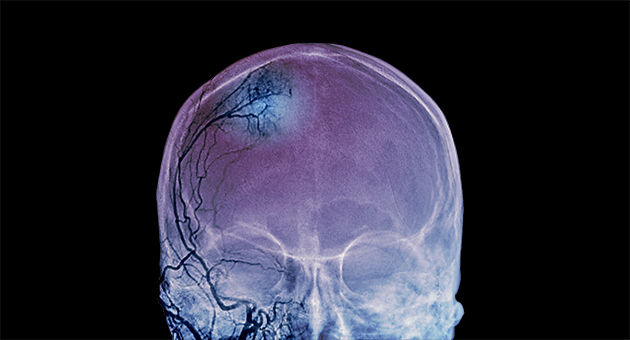

Nature突破:基于DNA甲基化,AI工具可诊断近100种脑瘤

3月15日凌晨,德国癌症研究中心(DKFZ)的Stefan Pfister及其同事的一项最新成果在线发表在顶级学术期刊《自然》(Nature),该团队研发了一款特别针对脑肿瘤的诊断AI工具。

对脑肿瘤治疗来说,正确诊断是提供治疗前的一项基础工作。目前已知的肿瘤有近100中类型,然而神经中枢系统的肿瘤是其中最难做到准确区分和诊断的。为解决这一难题,Pfister及其同事利用DNA甲基化数据训练了一种机器学习方法,最终可以根据甲基化数据对脑肿瘤进行自动分类。

研究团队获取了大概2800名癌症患者的甲基化数据,他们的AI工具最终可以诊断出91种肿瘤类型。随后,他们将这套AI工具在1104个中枢神经系统肿瘤病例上进行了测试。这些病例此前已经被医生人为诊断出结果,医生当时的误诊率是12%。